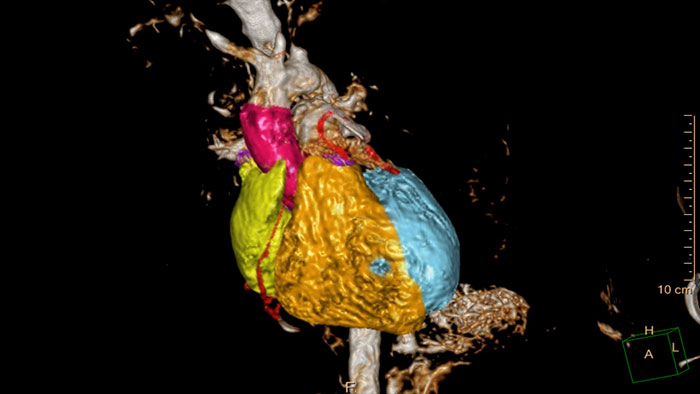

Comprehensive Cardiac Analysis (CCA)

CT Comprehensive Cardiac Analysis (CCA)

Comprehensive cardiac analysis

Designed to assist the user in viewing, analyzing and quantifying dedicated Cardiac CT Angiograms, mainly for coronary arteries analysis on Coronaries CT Angiogram (CCTA) data.

Benefits

• Cardiac function measurements based on automatic 3D model-based whole-heart segmentation.

• Automatic extraction and visualization of the coronary tree.

• The user can edit and modify the segmentation and the derived parameters.